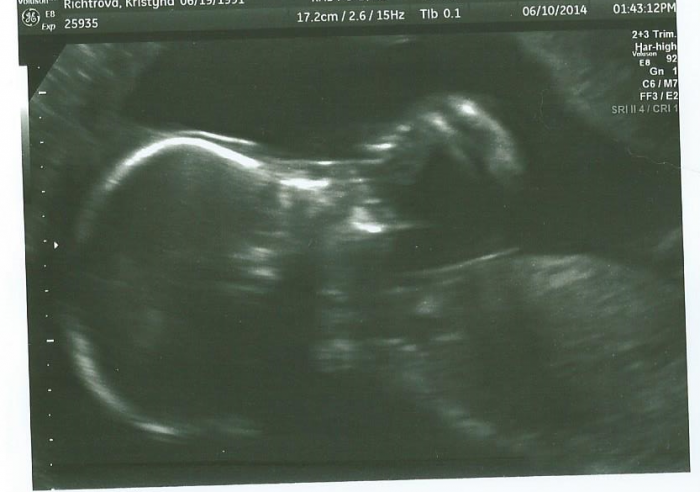

Ahojte holky, už dlouho jsem tu nic nenapsala.. Chci jen napsat,že jsem včera byla na screeningu v 20.tt a vše dopadlo  v pořádku..Rozárce krásně bije srdíčko :-)  Tak i Vy nemějte strach a pochybnosti :-)

[562569] Krasny obrazek Tynusko :-)